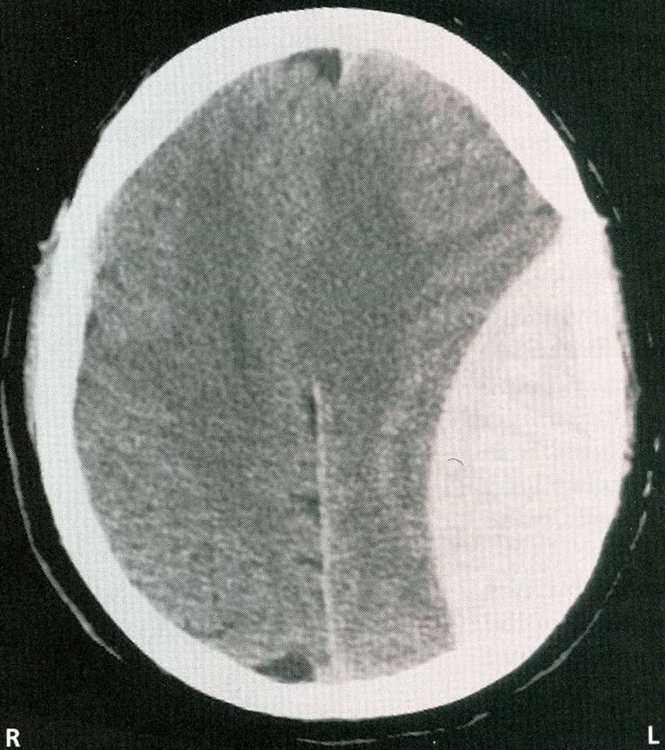

neck

brow, eye, face, lips, jaw, tongue, pharynx, larynx